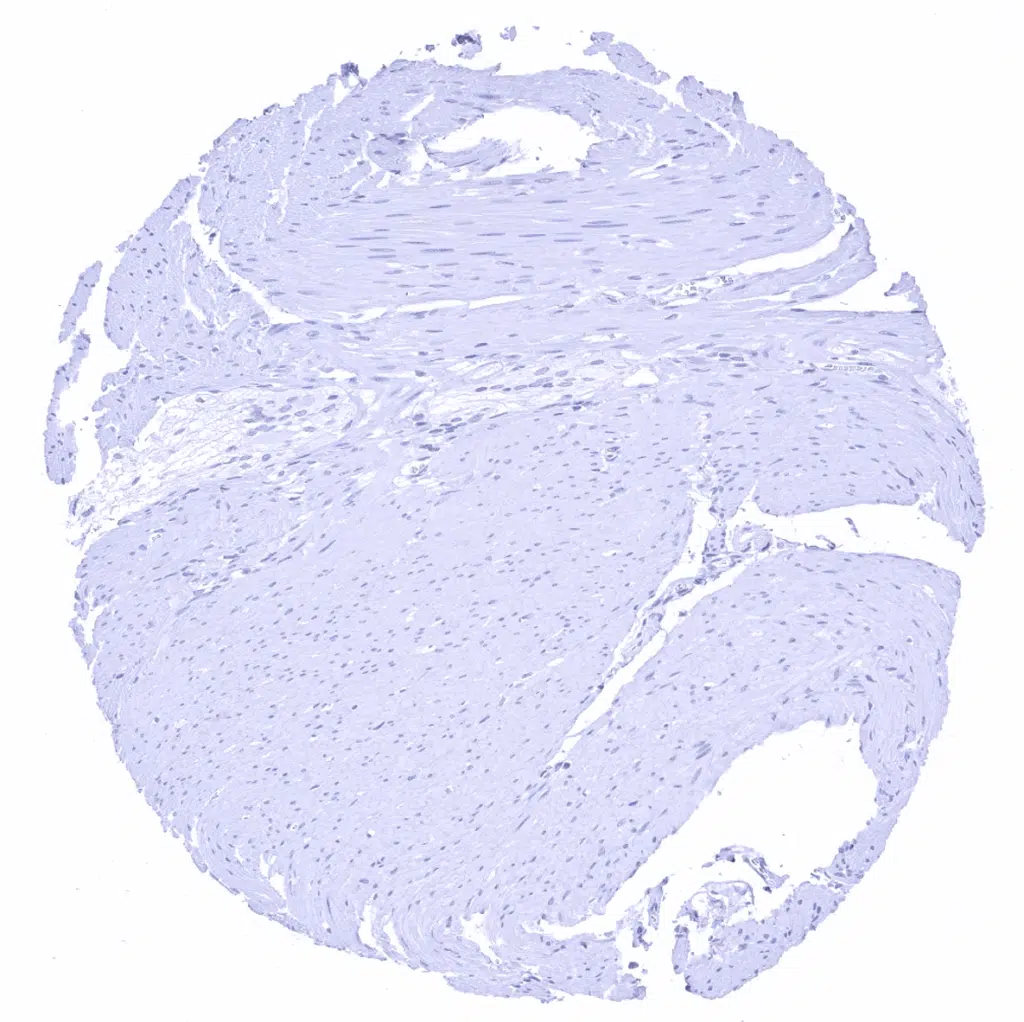

Uterus, myometrium